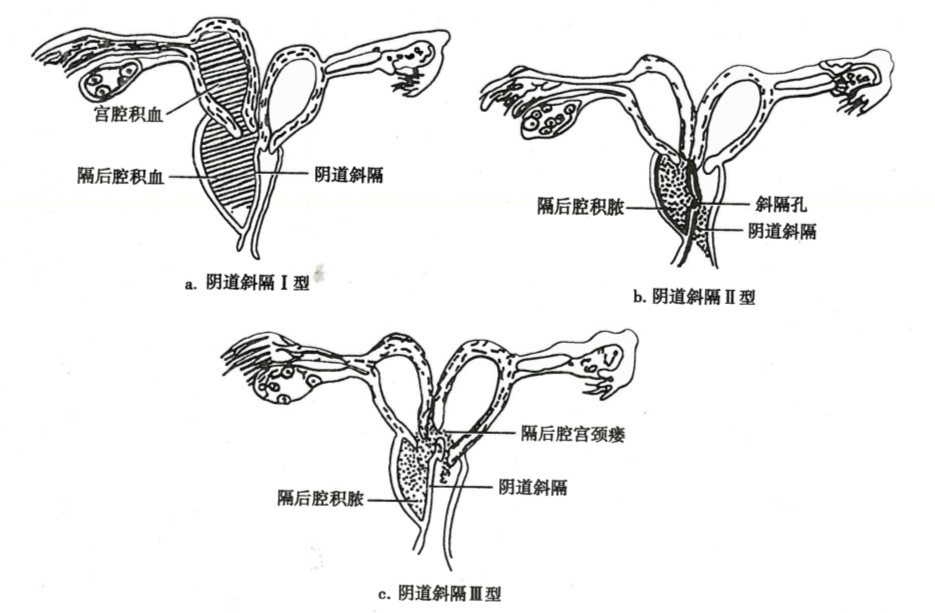

可分为三个类型(图22-6):①Ⅰ型为无孔斜隔,隔后的子宫与外界及另侧子宫完全隔离,宫腔积血聚积在隔后腔;②Ⅱ型为有孔斜隔,隔上有小孔,隔后子宫与另侧子宫隔绝,经血通过小孔滴出,引流不畅;③Ⅲ型为无孔斜隔合并宫颈瘘管,在两侧宫颈间或隔后腔与对侧宫颈之间有小瘘管,有隔侧子宫经血可通过另一侧宮颈排出,但引流亦不通畅。

图22-6 阴道斜隔综合征3种类型示意图

发病年龄较轻,月经周期正常,三型均有痛经,1型较重,平时一侧下腹痛;Ⅱ型有月经间期少量出血;Ⅲ型经期延长、也有月经间期少量出血。Ⅱ型和Ⅲ型若合并感染,可有脓性分泌物。妇科检查侧穹隆或阴道壁可触及囊性肿物,1型肿物较硬,伴增大子宫及附件肿物;Ⅱ、Ⅲ型囊性肿物张力较小,压迫时有陈旧血流出。局部消毒后在囊肿下部穿刺,抽出陈旧血,即可诊断。超声检查可见一侧宫腔积血,阴道旁囊肿,同侧肾缺如。必要时应做泌尿系造影检查。手术时机以经期为宜。做最大范围的隔切除,术后不需放置阴道模具。